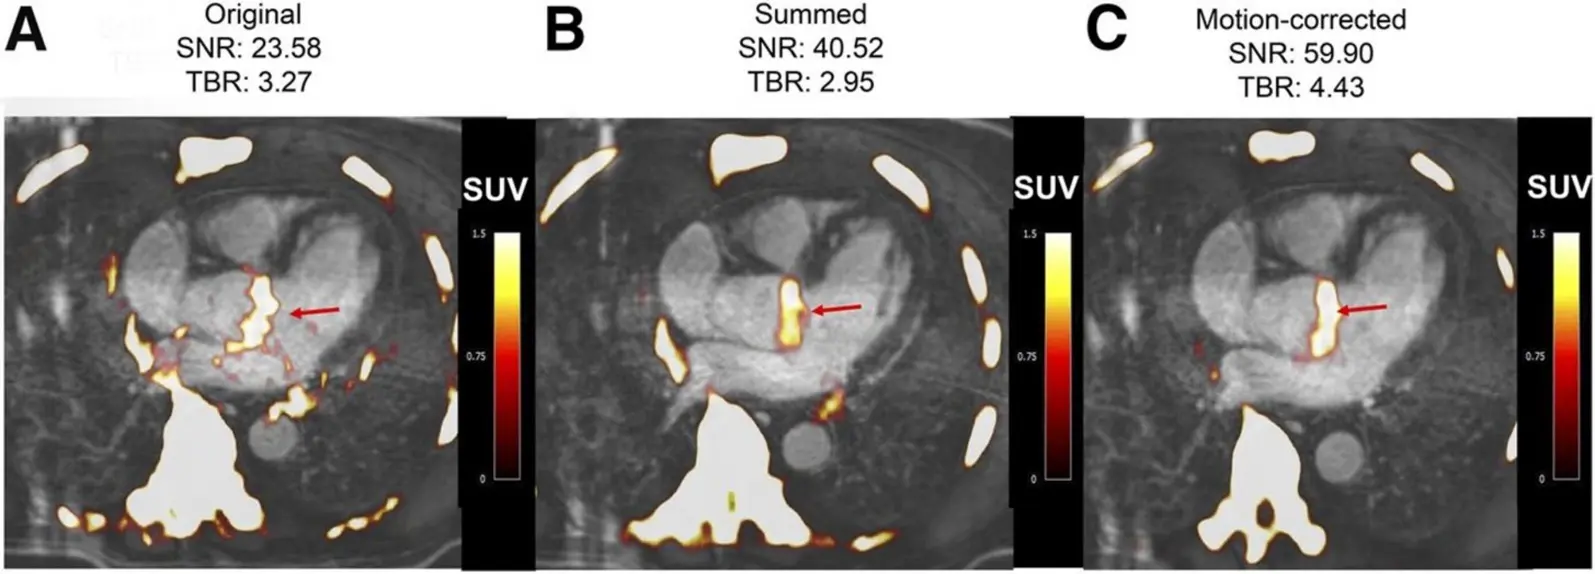

The use of 18F-FDG PET/CT in aortic stenosis (AS) has been explored in several studies (Figure 4), with initial work by Marincheva-Sancheva in 2011 showing increased valvular uptake in AS patients compared to controls, particularly in mild and moderate stages. This study found a significant correlation between increased uptake and disease progression, with patients having high 18F-FDG uptake more likely to experience progression of AS [57]. Subsequent studies confirmed the feasibility and reproducibility of PET/CT imaging in AS, with 18F-NaF demonstrating a stronger correlation to AS severity than 18F-FDG [58]. A prospective study showed that 18F-NaF uptake was highest in severe AS cases, and both 18F-NaF and 18F-FDG predicted disease progression and adverse outcomes, with both being independent predictors of cardiovascular events and aortic valve replacement (AVR) [59]. Further research has identified potential therapeutic targets, such as lipoprotein(a) (Lp(a)) and oxidized phospholipids (OxPL), with higher 18F-NaF uptake in patients with elevated Lp(a), suggesting that targeting these pathways may slow AS progression [60]. Additionally, 18F-NaF PET/CT has shown promise in evaluating bioprosthetic valve degeneration, correlating well with histological changes and predicting valve dysfunction [61]. Ongoing trials, such as SALTIRE 2, are using 18F-NaF to assess the impact of therapies like denosumab and alendronate on valvular calcification. While CT calcium scoring provides similar predictive value, advancements in PET/CT technology may improve its clinical utility, particularly for bioprosthetic valves.

Figure 4. Fused 18F-fluoride PET/contrast-enhanced MR angiograms of aortic valve of 60-y-old man with aortic stenosis. Shown are original diastolic gate (A), summed image (B), and motion-corrected image (C) with focal 18F-fluoride uptake (arrows).

PET/MR is an emerging imaging technique that combines high-resolution MRI with sensitive PET molecular imaging, offering advantages such as superior tissue characterization, motion correction, and reduced radiation exposure. However, its clinical adoption remains limited due to the high cost and technical challenges, particularly in cardiac applications. Notably, PET/MR employs a different method for attenuation correction, based on proton density, with some limitations in cardiac studies due to motion artifacts and mis-segmentation. Despite these challenges, PET/MR has shown promise in assessing aortic stenosis, with early studies by Doris et al. demonstrating increased 18F-fluoride uptake and improved signal-to-noise ratios in the aortic valve region [62]. Additionally, PET/MR has been used to assess myocardial infarction and inflammatory heart diseases like sarcoidosis, myocarditis, and endocarditis, as well as to differentiate subtypes of cardiac amyloid [63]. The technique has particular promise for assessing chronic conditions like bicuspid aortic valve disease, given its reduced radiation exposure, which is important for younger patients. PET/MR is being explored as a tool in trials like BASIK2 to evaluate the effect of vitamin K2 on valvular calcification in patients with bicuspid aortic valve disease [64]. Furthermore, a validation study comparing PET/CT and PET/MR in coronary artery disease and aortic stenosis is underway to determine if PET/MR can provide comparable results to PET/CT. Ongoing studies may establish PET/MR’s role in enhancing our understanding of the temporal relationship between inflammation, fibrosis, and calcification in aortic stenosis.